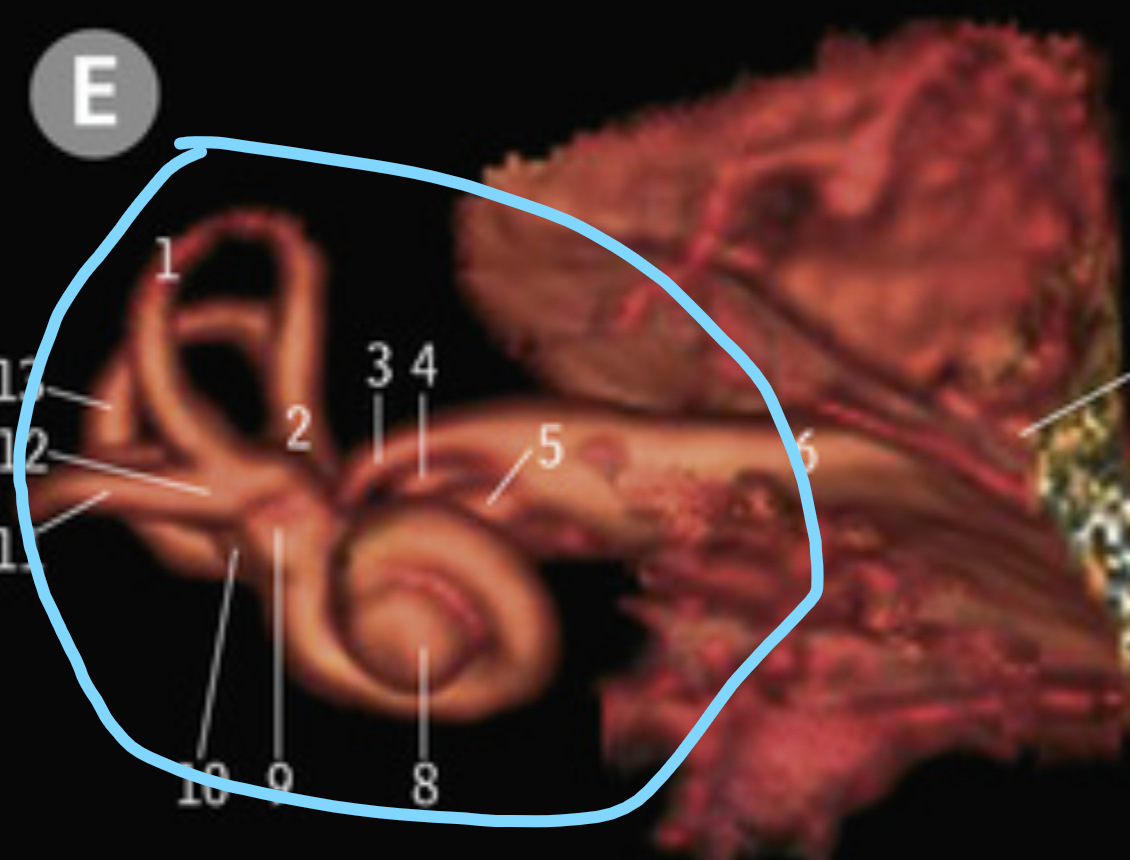

What is circle in blue

Inner ear

16

Middle ear